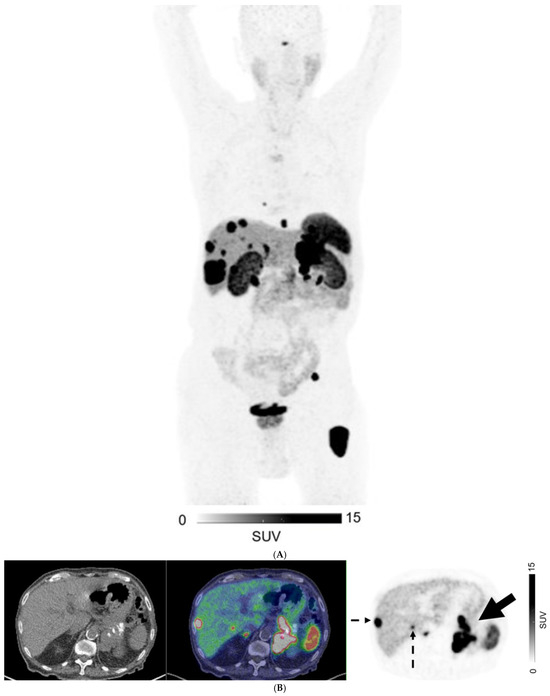

Figure 3.

A 76-year-old man with well-differentiated G3 pancreatic neuroendocrine tumor (SUVmax 131.5, Krenning score 4), with bilobar liver metastases on CT. 68Ga-DOTATATE PET (A) MIP image; (B–D) Axial images: CT (left), fused PET/CT (middle), and PET (right). PET shows an intensely-avid locally advanced pancreatic tail mass (SUVmax = 132; solid arrow in (B)), liver metastases (biopsy proven; dotted arrows in (B,C)), peritoneal deposit (arrowhead in (C)) and bone metastases (open arrows in (C,D)).